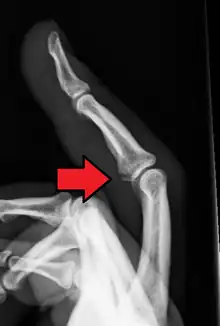

| Avulsion fracture of the proximal middle phalanx on the palm side | |

An avulsion fracture is a bone fracture which occurs when a fragment of bone tears away from the main mass of bone as a result of physical trauma. This can occur at the ligament by the application of forces external to the body (such as a fall or pull) or at the tendon by a muscular contraction that is stronger than the forces holding the bone together. Generally muscular avulsion is prevented by the neurological limitations placed on muscle contractions. Highly trained athletes can overcome this neurological inhibition of strength and produce a much greater force output capable of breaking or avulsing a bone.